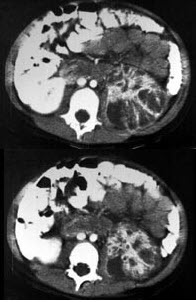

男,5岁,有尿路感染伴急性发热,CT增强扫描如图所示,最可能诊断为( )

A、左侧肾炎

B、左侧肾脓肿

C、左侧急性肾盂肾炎

D、左侧黄色肉芽肿性肾盂肾炎

E、左侧慢性肾盂肾炎

点击查看答案